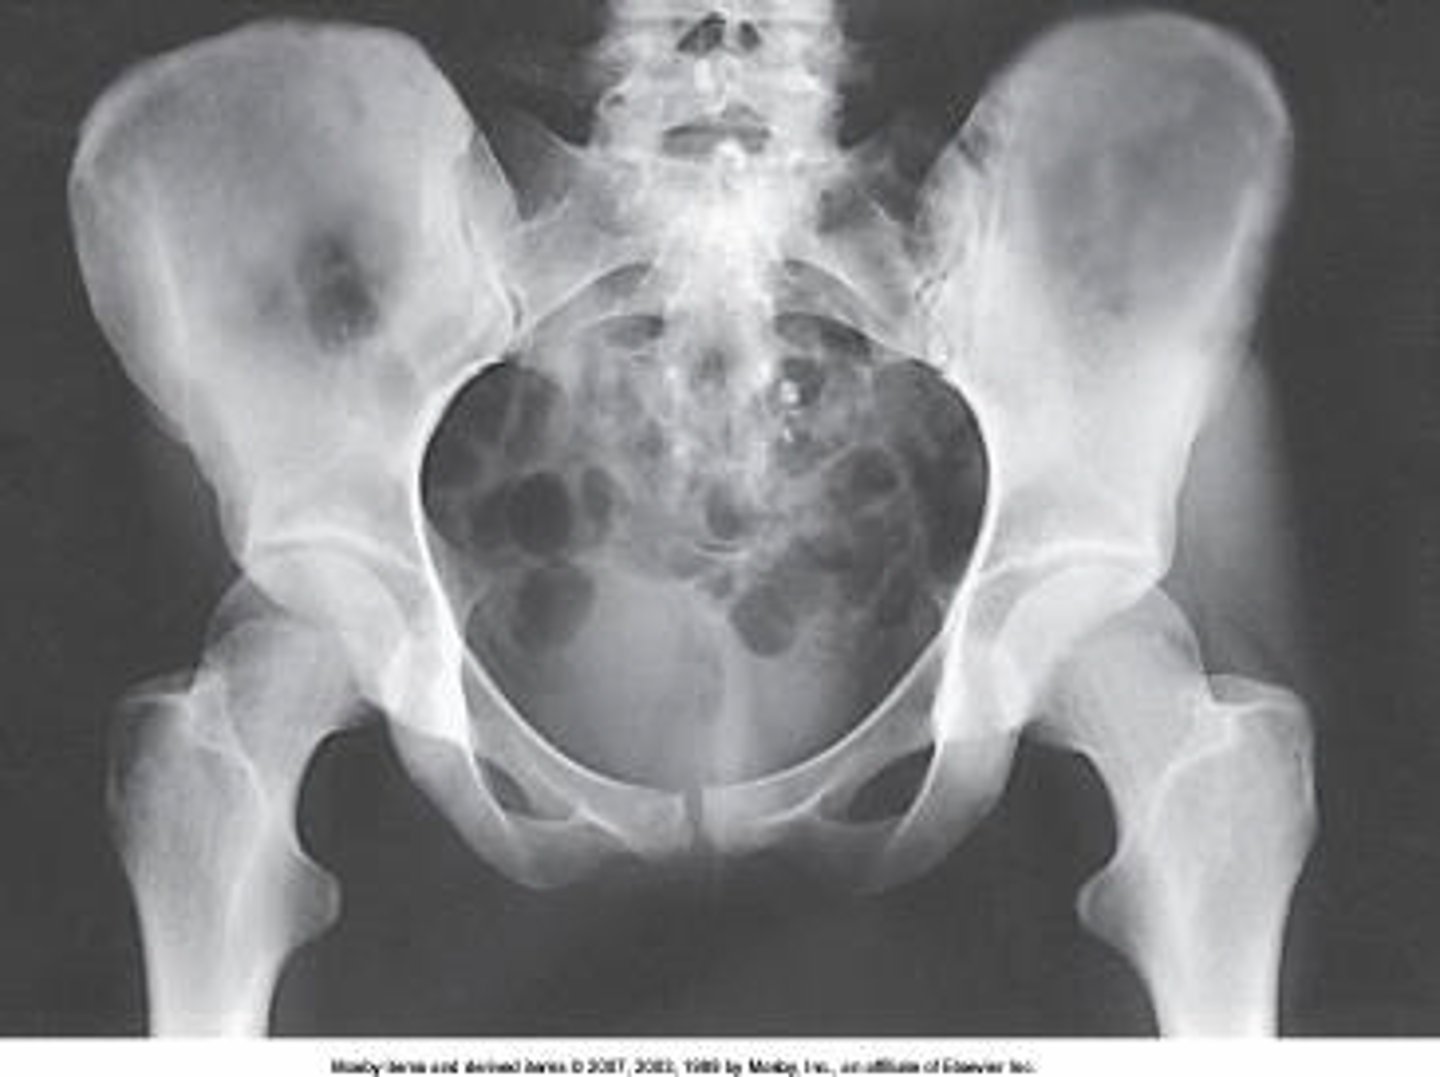

obturator foramen

The area of anatomy indicated on the figure above is the:

pubis

ischium

acetabulum

ASIS

What anatomy is labeled as letter C in the image below?

Iliac crest

Ala of ilium

AIIS

What anatomy is labeled as letter A in the image below?

Femoral head

Femoral neck

Greater trochanter

The lower limbs were not internally rotated.

What positioning error is evident in the image below?

None. This image meets all evaluation criteria for this projection.

The lower limbs were not externally rotated.

The knees were not flexed to reduce lordotic curve.

Lesser trochanter

What anatomy is labeled as letter B in the image below?